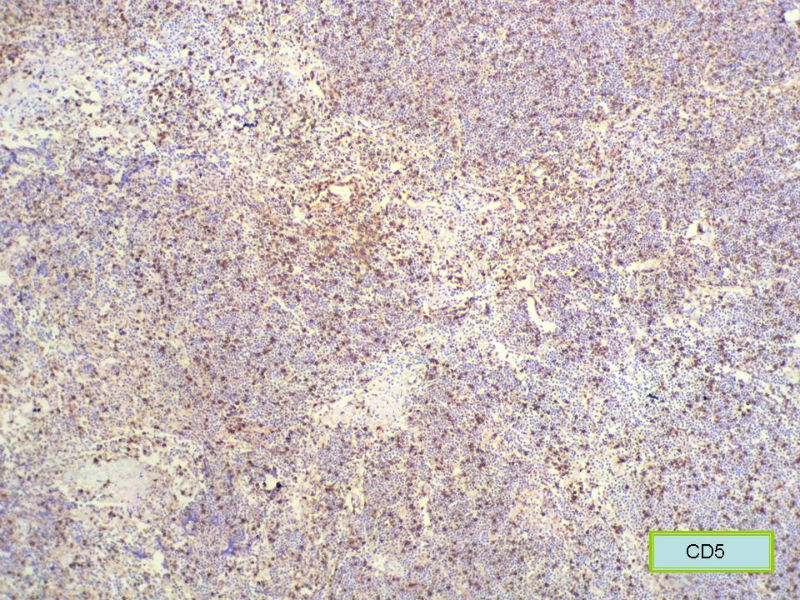

请再标记CD20和CD79a!图片中阳性不明确,根据T细胞标记看,应该是B细胞结节。Ki67散而少,不支持低级别滤泡性淋巴瘤,若B细胞弥漫阳性,则是惰性B细胞非霍奇金淋巴瘤,首先考虑套细胞,然后是边缘区淋巴瘤。不做生发中心标记,Bcl-2在小B细胞淋巴瘤分类中无意义。

赞成以上专家的讨论,根绝病史,HE形态考虑小细胞病变,CD3、CD5散在+,还是倾向淋巴造血系统病变,CD20、CD79a阳性不明确,可以考虑复查,加做PAX-5,核阳性容易判断,另再加做鉴别其它小细胞肿瘤的抗体:CD99、CD43、CyclinD1、CK、CgA、Syn等,了解病史:骨髓、末梢血、肝、脾等。

本例是发生在特殊部位“结膜下”,HE肿瘤细胞形态形态一致,形似单核样B细胞。B细胞标记若明确阳性,诊断MALT是挺合理的。

CD20(+),Kappa(+),ki-67(+)>2%,Lambda(+),Pax-5(+),符合粘膜相关淋巴瘤。